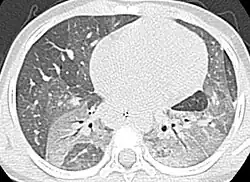

Chest computerized tomography scan showing diffuse ground-glass opacities with air-bronchograms in the upper lobes and the left lower lobe.

Thoracic high-resolution computed tomography (HRCT) often shows signs of DIP,[17] however, HRCT has only been reported on in one study. HRCT shows a ground-glass appearance.[20]